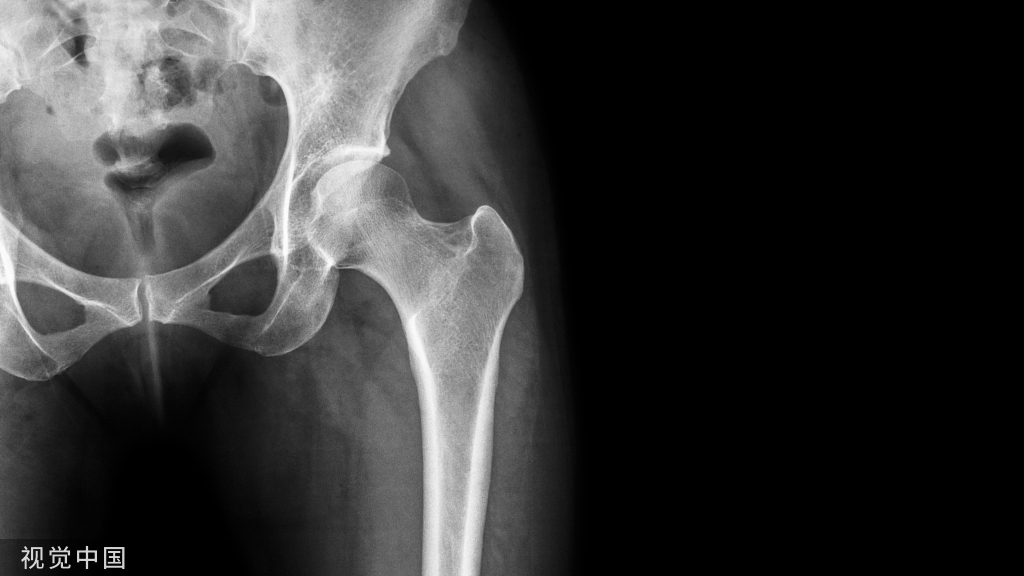

年龄:2岁性别:男病史:O型腿,走路困难

X线

X线见双胫骨内翻,双胫骨近侧干骺端增宽,内侧皮质增厚呈鸟嘴样

结论:Blount病

当临床出现进展性内翻,同时平片中胫骨近端出现特征性改变(干骺端内侧增宽、规则,骨皮质增厚且呈垂直走形呈鸟嘴样;内侧骨骺高度减小)时可以明确诊断。